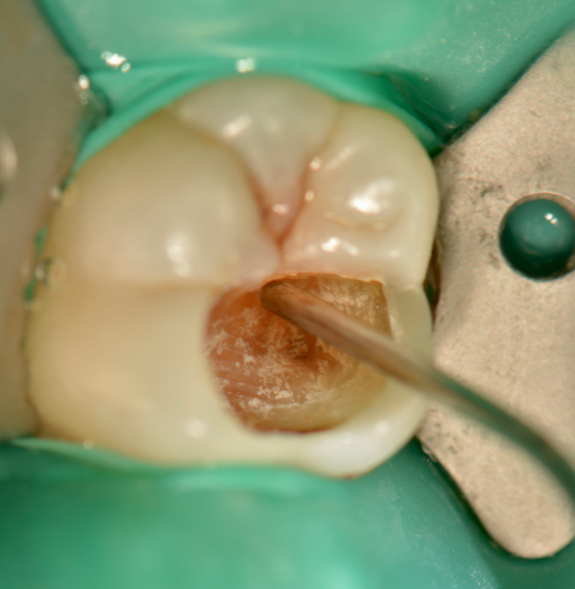

Fig. 3. Excavation with polymer bur

Fig. 4. Carious lesion after initial excavation